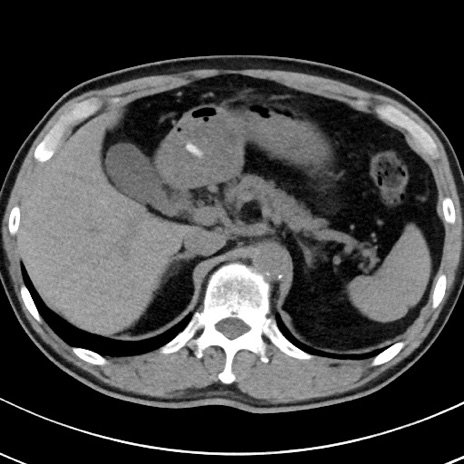

【腹部TIPS】症例29 参考症例 CT(横断像)

症例

70歳代男性